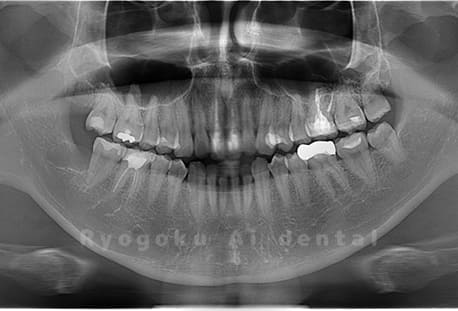

Case02

- 原因

- 下顎の水平埋伏智歯

- 治療内容

- 下顎の水平埋伏智歯を抜歯

<リスク・副作用>

手術後は痛み、腫れ、痺れなどの副作用が生じる場合があります。